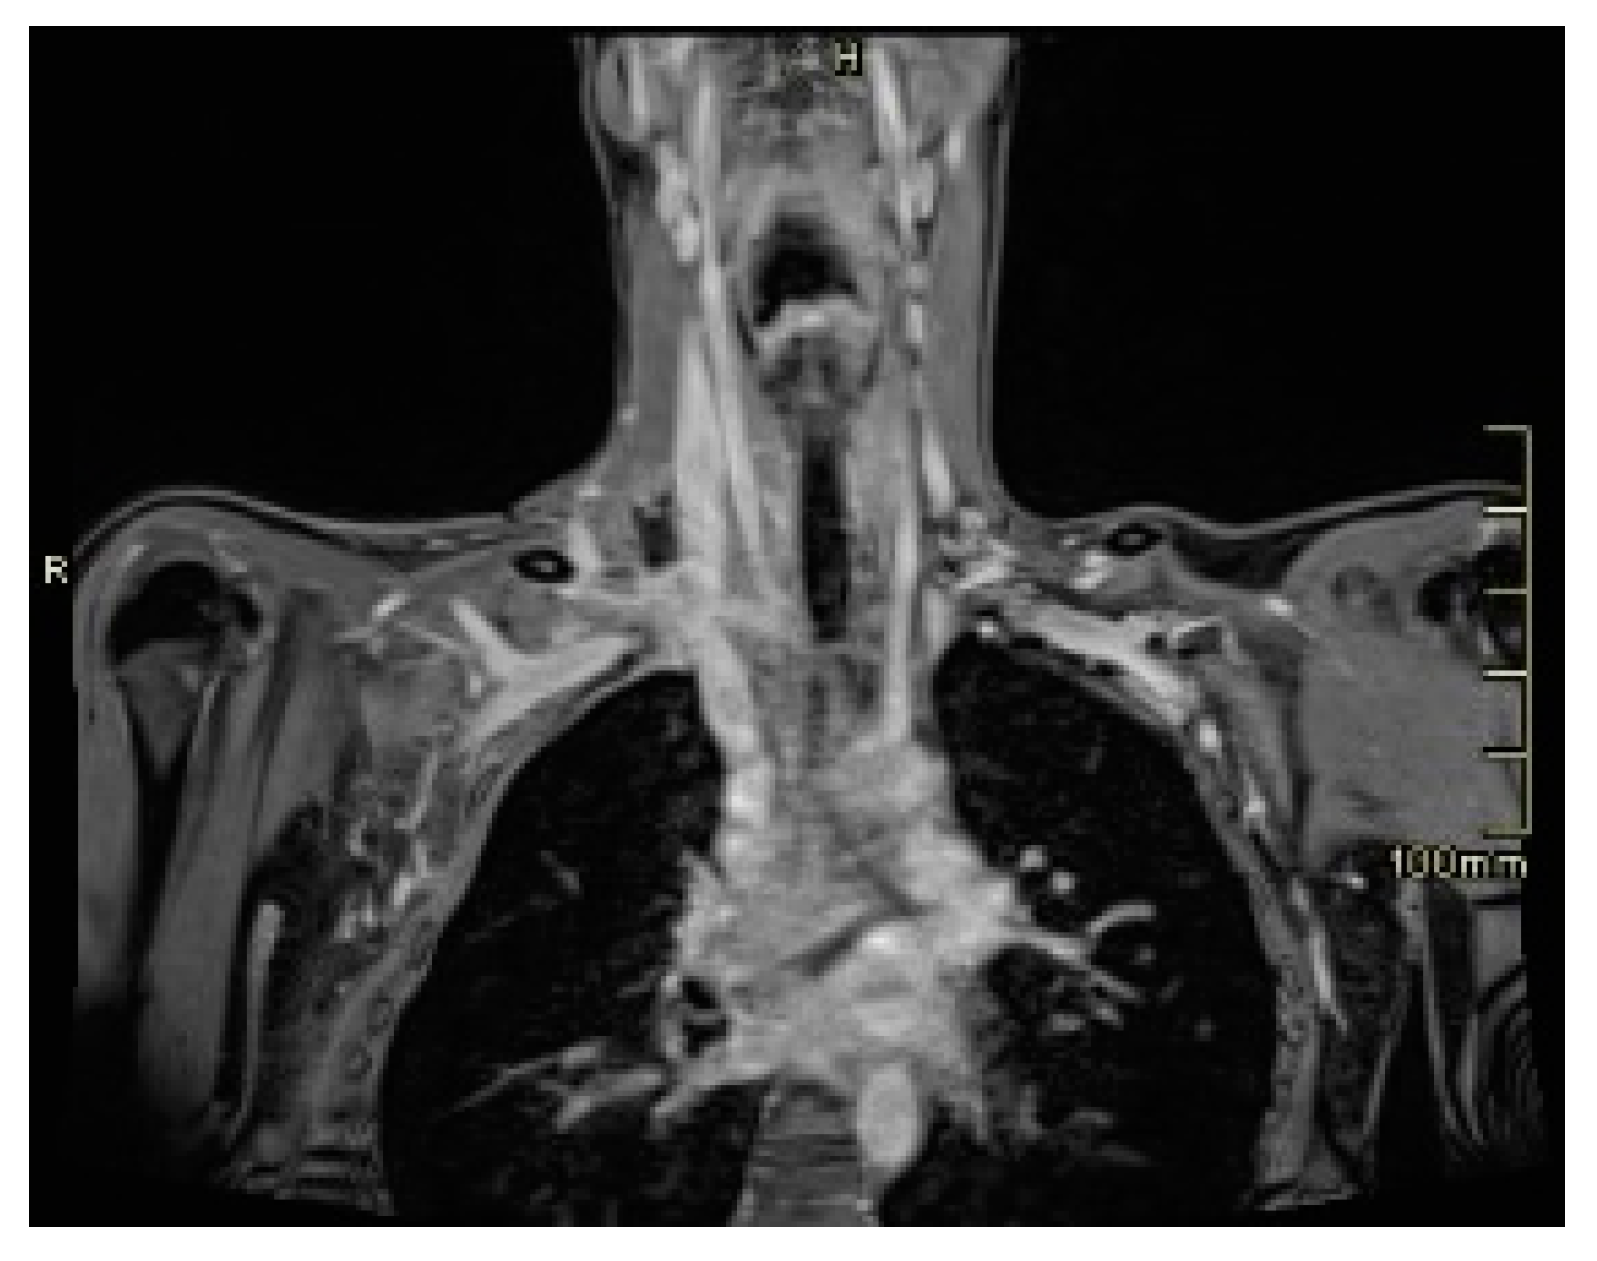

2. Case Presentation